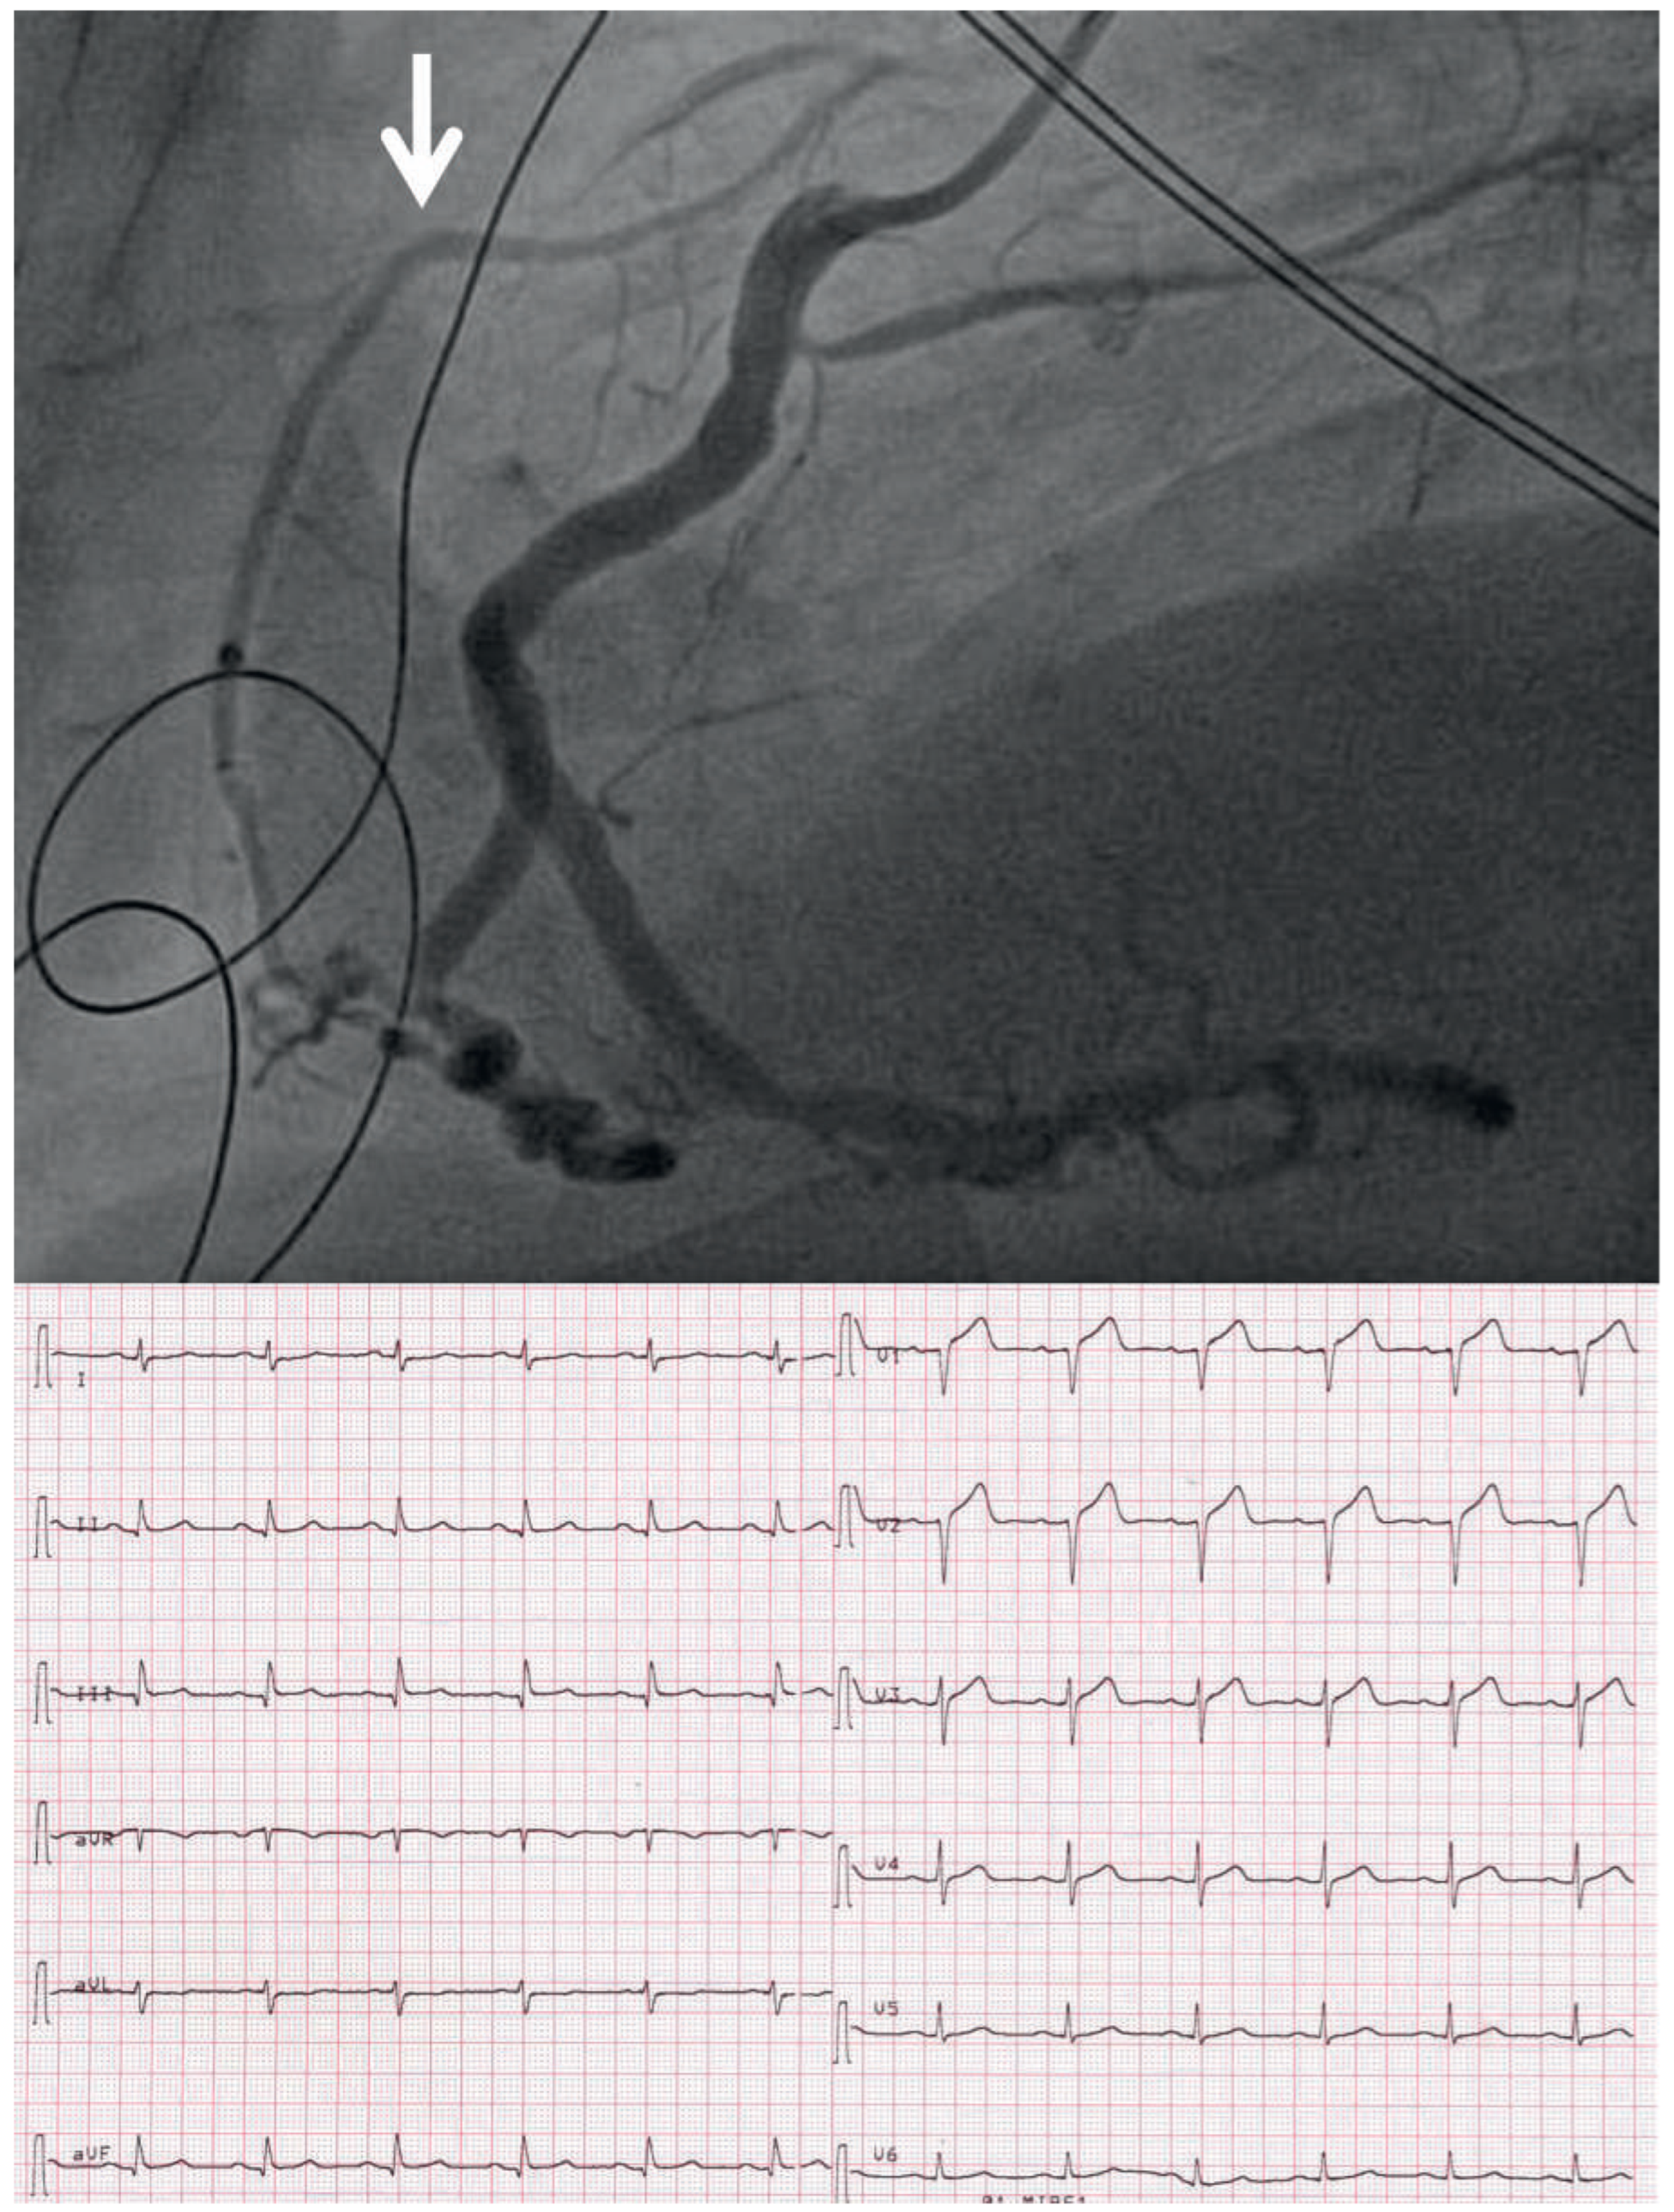

The RCA was recanalised by use of thrombus aspiration, balloon dilatation and implantation of a drugeluting stent. The final angiogram (Figure 5 top) demonstrated that the chronically occluded LAD (arrow) was very well collateralised by the RCA. Thus, with the acute occlusion of the RCA there was acute ischaemia in the territories of both the RCA and the LAD. The LAD was occluded after the origin of the first diagonal branch, and thus there was no ST-segment elevation in leads I and aVL but ST-segment depression in those leads (“reciprocal” to the ST-segment elevation in leads II, III, and aVF). The ECG obtained immediately after PCI revealed significant ST-segment resolution (Figure 5 bottom). A similar ECG could have been recorded in the case of the acute occlusion of a large LAD after the origin of the diagonal branch if the LAD were running around the cardiac apex to the inferior wall, and the RCA were therefore relatively small.

Figure 5. Top: angiogram after percutaneous coronary intervention (PCI) of the right coronary artery (RCA), LAO 90% (same angiographic projection as Figure 3, panel D). The RCA is open, and via the RCA and collaterals the LAD now becomes visible (arrow). Bottom: ECG after PCI.